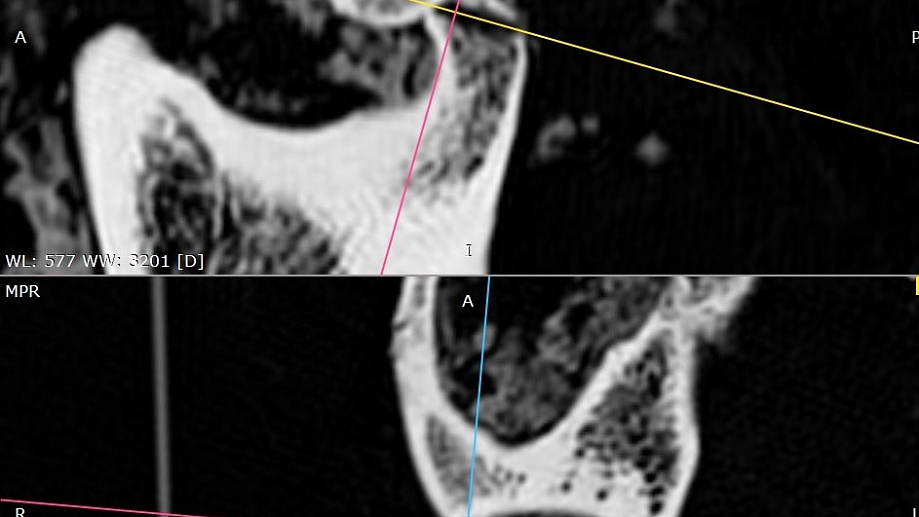

Experts at Novosibirsk State University (NSU), Russia, used a CT scan to examine her skull, hidden beneath layers of mummified tissue.

The scan showed she had suffered a severe head injury in life – her right jaw joint was destroyed, ligaments torn, and her lower jaw displaced beneath the skin.

The scan revealed two small holes deliberately drilled in the bone during her lifetime, each surrounded by a ring of new bone growth – clear evidence of healing.

Traces of elastic material, probably horsehair or tendon, were found inside the holes, suggesting they were used as a primitive surgical ligature to stabilise her jaw.